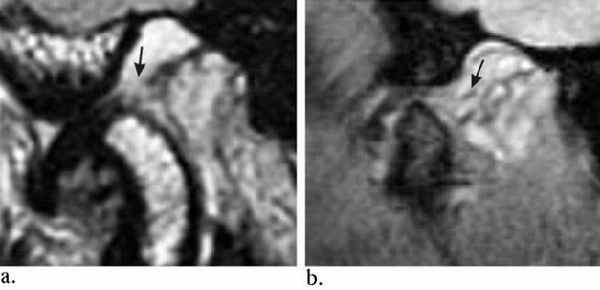

(Слева) На косой сагиттальной МРТ (Т1 ВИ) ВНЧС с закрытым ртом визуализируется задний пучок диска, находящийся в нормальном положении относительно мыщелка.

(Справа) На косой сагиттальной МРТ (Т1 ВИ) ВНЧС у этого же пациента визуализируется задний пучок диска, остающийся спаянным с самыми верхними отделами суставной ямки. Область соединения переднего пучка с переходной зоной находится между мыщелком и суставным возвышением. Отсутствует трансляция диска относительно заднего ската суставного возвышения.